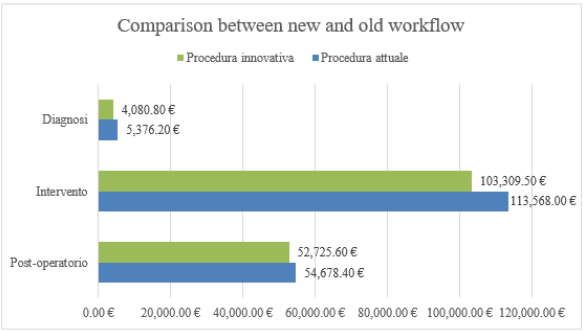

Innovative Procedure Profits

Using a three-dimensional reproduction with the new workflow allows to save money in a cost analysis. In the diagnosis phase the number of orthopedic visits fell from 3 to 2 for each patient decrease by 33.4% or saving 18 €/patient. Moreover, the 3D model allows to bypass the first radiological step so the number of radiological visits per patient is halved avoiding the expense of 21 €/ patient. The traditional surgical intervention was about 60 minutes average. Using the prototype, the time frame should be reduced by 15 minutes or 25% less This reduction in use of the operating room costs 206.75 €/ patient less. Finally, studying the case on the 3D prototype decrease the recurrence rate of 15% compared to the traditional case (only CT used). Moreover, with the innovative methodology, one less case of relapse in a year occurs (2 cases compared to 3 in the traditional procedure). In the worst-case scenario, if all 2 recidivist patients need re-intervention, the total saving is about 5094.32€ (new TC: 86.5 €; inspection visit: 18 €; the surgery: 3380 €; post-operative phase: 1627.32 €). (Table 9) summarizes the improvement rates of the new workflow in terms of money saving per year. Looking at the (Figure 21), the saving in the diagnosis phase is 1295,4 €/year, in the surgery phase it is 10258.5 €/year while in the post-operative phase a is 1952.8 €/year for a total saving of € 13,526.7 €/year. It results in a total reduction in spending of 7/8 % per year.

It is also necessary to consider the expense due to the cost of creating a sterilizable prototype, i.e 107.42 €/model since the only suitable from the list before mentioned is HT-PLA. Considering that the number of patient’s 3D models in one year is average 27 (25 new cases and 2 repeat offenders), the total cost is approximately 2900 €/year. Finally, the cost of the innovative method is therefore around 10607 €/year, which allows an annual saving of 6.1 %. The result obtained is based on the worst hypothesis for recurrence cases where re-surgery is considered necessary. It was considered in also the case of zero recidivism for both procedures. Taking account that the production cost of 25 prototypes is 2686 €, the total cost of the proposed procedure is 102943 €/year. The advantages brought by the use of the prototype make the innovative procedure more tempting because of the lower costs also in this case.